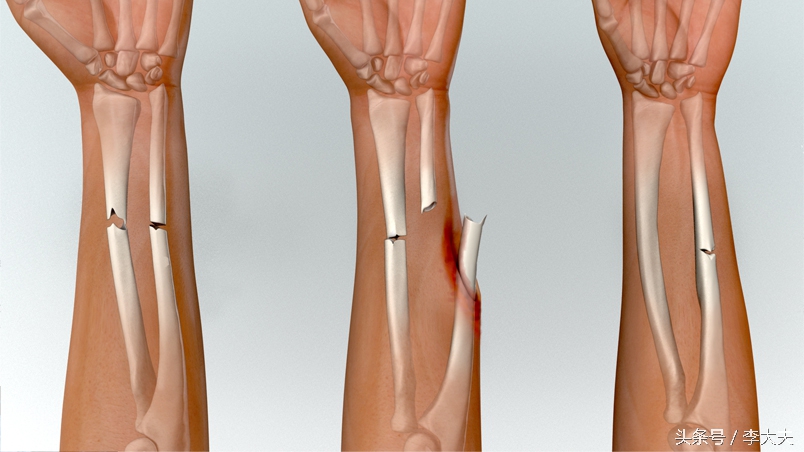

上肢前臂双骨折